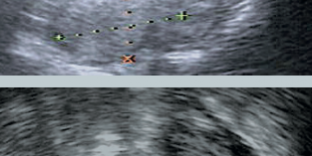

L’image 2 montre l’annexe droite.

Il existe d’une part 2 petites images ovariennes vraisemblablement folliculaires et d’autre part, en dehors, une image d’environ 10 mm, formée d’un centre transonore et d’une couronne échogène vascularisée dont on ne peut pas préciser la nature.

L’image 3, obtenue après modification de l’angle de vue, met en évidence au contact des follicules visualisés une autre image ovalaire, d’environ 15 mm de diamètre moyen, cerclée d’une intense couronne vasculaire.

Cet aspect est très en faveur d’un corps jaune. Au total, cette échographie ne retrouve pas de grossesse intra-utérine et met en évidence 2 images annexielles droites vascularisées. C’est une de trop !

Dans un tel tableau clinique, la présence de 2 images annexielles de ce type signe le diagnostic de GEU associée à un corps jaune. La patiente est adressée au chirurgien.